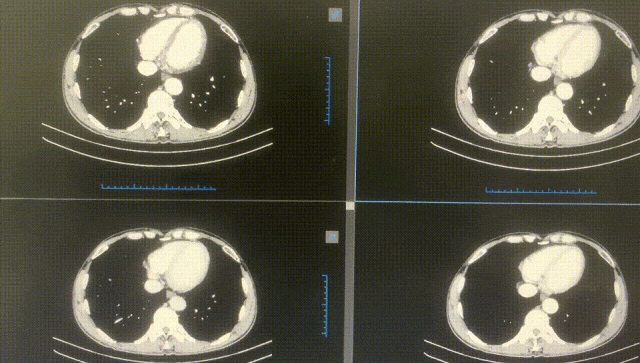

術后